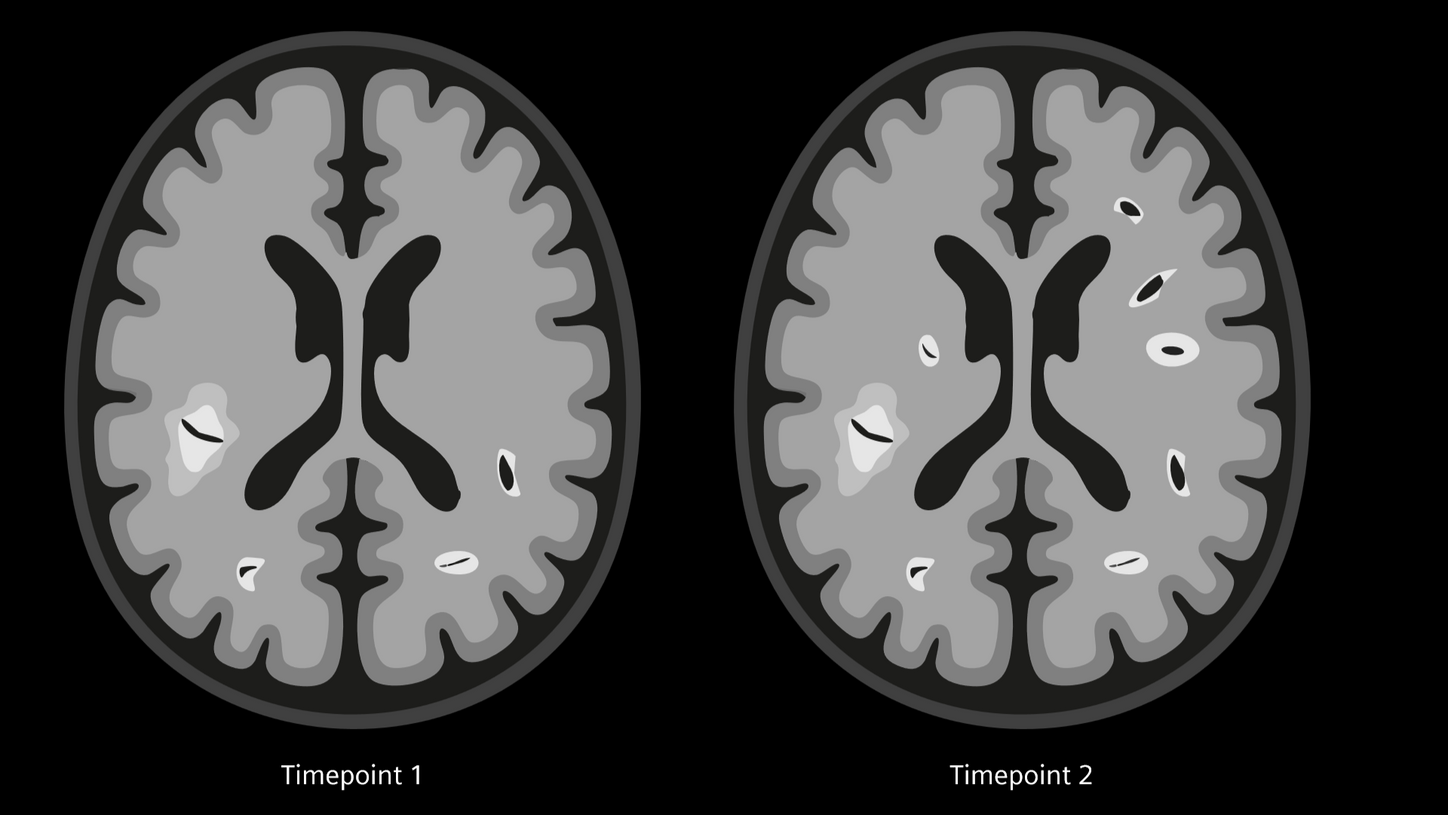

Dissemination in time (DIT)

New lesions at two different points in time

DIT refers to the development of new lesions within the CNS over time, meaning that during different time points of MRI follow-up new lesions can be found which have not been seen before. DIT can be demonstrated via new WMH on T2-weighted imaging as shown above, or new contrast-enhancing lesions in T1-weighted MPRAGE.